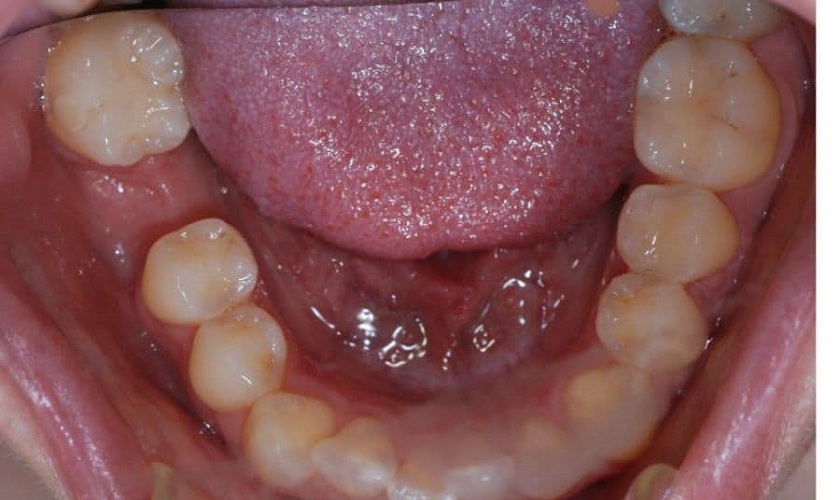

Răng cấm chính là một trong 2 chiếc răng hàm có vai trò chủ lực trong quá trình ăn nhai của mỗi con người. Hơn nữa, bên dưới răng cấm lại là khu vực vô cùng nhạy cảm vì có rất nhiều dây thần kinh. Cho nên việc nhổ răng cấm vẫn luôn được các bác sĩ hạn chế ở mức tối đa.

Răng cấm là những chiếc răng có vai trò rất quan trọng trong việc nhai, nghiền thức ăn trên cung hàm. Do đó, việc bảo tồn răng cấm luôn là sự ưu tiên hàng đầu và còn là kim chỉ nam trong các kỹ thuật nha khoa hiện nay.

Vì răng cấm nằm trong nhóm răng cối lớn, có trách nhiệm nghiền nát thức ăn. Cho nên nếu thiếu răng số 6 thì chức năng ăn nhai của bạn sẽ bị ảnh hưởng khá nghiêm trọng. Tình trạng mất răng cấm còn khiến răng số 7 phải một mình “cáng đáng” hết mọi trách nhiệm nên khả năng nghiền thức ăn sẽ bị suy giảm một cách rõ rệt.